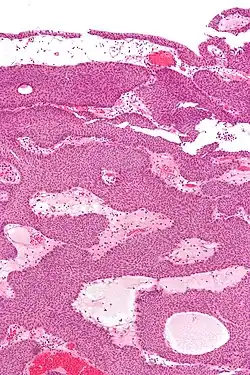

| Micrograph of an inverted papilloma of the urinary bladder; H&E stained | |

Histopathology representing an inverted papilloma of the urinary bladder that was cystoscopically resected. Hematoxylin and eosion stain. -